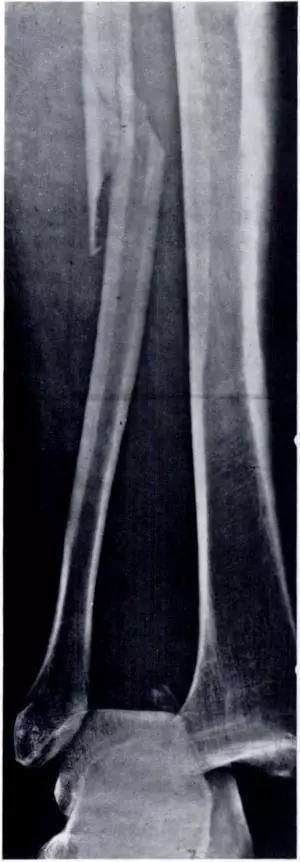

5. Maisonneuve 骨折

腓骨近端骨折伴内踝骨折及三角韧带断裂。

(来源:Radiopaedia)